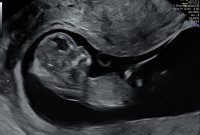

Alt ser fint ut, og jeg ble satt frem 8 dager til 12+5, fikk også en video av en liten sprellende baby:Heartred